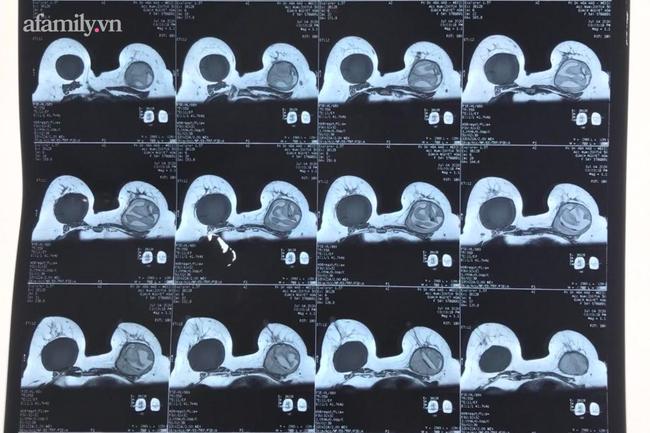

Hình chụp X-quang cho thấy chị H. bị vỡ túi ngực nhân tạo bên trái.

Tại khoa Tạo hình - Thẩm mỹ, sau khi thăm khám và thực hiện xét nghiệm kiểm tra, bác sĩ cho biết chị H. bị vỡ túi ngực nhân tạo bên trái, nách trái có hạch lớn, bầu ngực bị biến dạng.